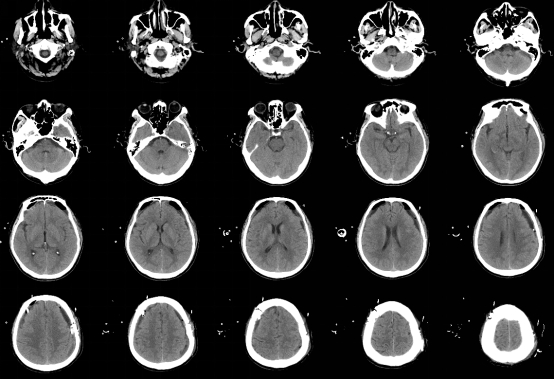

近期,我科完成了一例慢性硬膜下血肿手术。该患者男性,63岁,是因为“摔伤头部半年,记忆力下降,思维迟钝大约20天” 在当地医院就诊,行颅脑CT提示双侧额颞顶部慢性硬膜下血肿,脑疝,CT片可见慢性血肿有很多分隔。当地医院医生建议患者分二次行双侧开颅手术,清除硬膜下血肿,创伤很大,手术后需要住ICU,而且住院时间很长,费用高。患者家属犹豫不决,担心手术风险,于是带着CT片到我科门诊咨询。门诊孟主任阅片后告知家属,我科可以通过神经内镜微创手术治疗慢性硬膜下血肿,可以一次手术,手术创伤小,风险低,费用少,住院时间短,大约10天左右就可以出院,而且手术后不需要住ICU,于是家属当天下午就驱车带患者来我科住院。管床医生涂医生仅用一天时间就完成全部术前检查,第二天就安排了手术。手术中通过神经内镜观察到慢性硬膜下血肿有很多的分隔及纤维组织,与可自行流出的液态慢性血肿相比,该患者需通过吸引器反复仔细吸除血肿分隔及纤维组织,同时反复盐水、双氧水冲洗,避免血肿残留及复发。手术过程很顺利,术后患者清醒,无任何神经功能障碍及并发症,手术后10天患者治愈出院,在后期随访观察中,未见慢性血肿复发。

术后第1天CT

术后第4天CT

随访CT